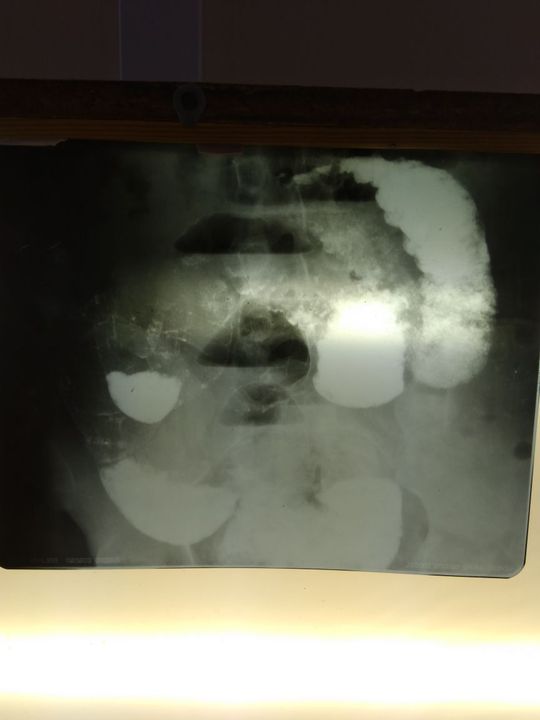

Ulcerative colitis